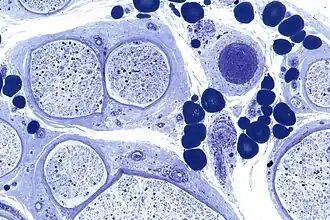

Description de cette image, également commentée ci-après

En neurologie, une neuropathie est un terme médical caractérisant, au sens large, l’ensemble des affections essentiellement du système nerveux périphérique, c'est-à-dire des nerfs moteurs et sensitifs des membres, des nerfs du système nerveux autonome qui commandent les organes ainsi que plus rarement du système nerveux central.

Les neuropathies périphériques comprennent les mononévrites, les multinévrites, les polynévrites, les polyradiculonévrites chroniques et les maladies de Charcot-Marie-Tooth.